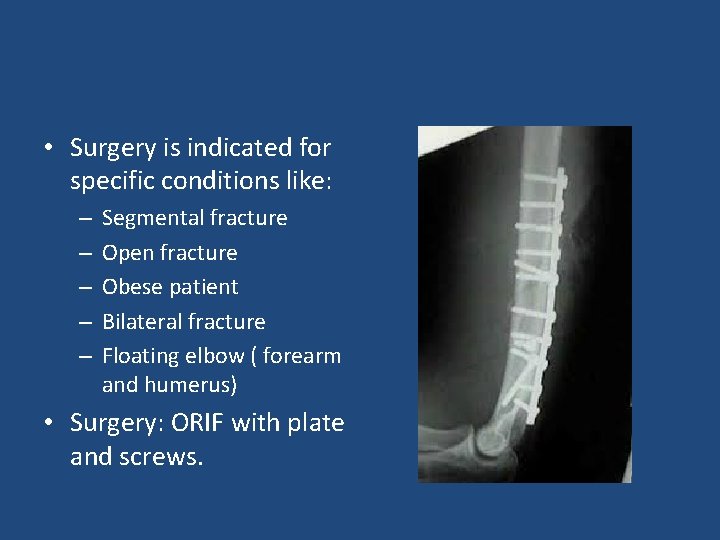

• Surgery is indicated for specific conditions like: – – – Segmental fracture Open fracture Obese patient Bilateral fracture Floating elbow ( forearm and humerus) • Surgery: ORIF with plate and screws.